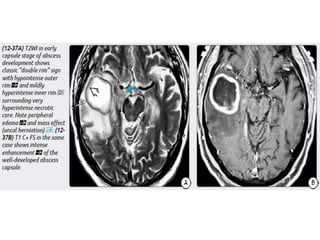

Abscess

Abscess is initiated by focal intracranial infection as an area of cerebritis

and evolves into a collection of pus surrounded by a vascularized

capsule.

4 stages of evolution

Abscess Abscess is initiatedby focal intracranial infection as an area of cerebritis and evolves into a collection of pus surrounded by a vascularized capsule. Size- 5 mm up to several centimetres. Age – most common in 3rd and 4th decades. Infants and neonates - its rare (may occur as complication of bacterial meningitis)

4 stages ofevolution